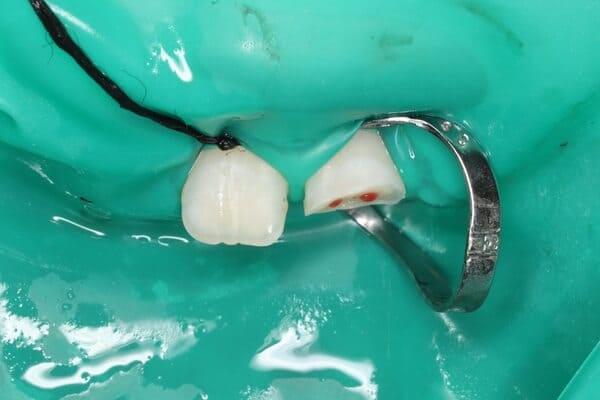

1. ​Відламалася частина зуба (скол емалі або дентину)

2. Зуб вибитий повністю (на місці зуба порожня лунка).

3. ​Зуб змінив положення (вдавився всередину або нахилився).

1. Знайдіть зуб або його уламок.

2. Тримайте правильно: Беріть зуб лише за коронкову частину (білу верхівку). Не торкайтеся кореня!

3. ​Зберігання: Не мийте зуб водою і не тріть його. Помістіть його у молоко або фізіологічний розчин. Це критично важливо для збереження життєздатності клітин кореня.